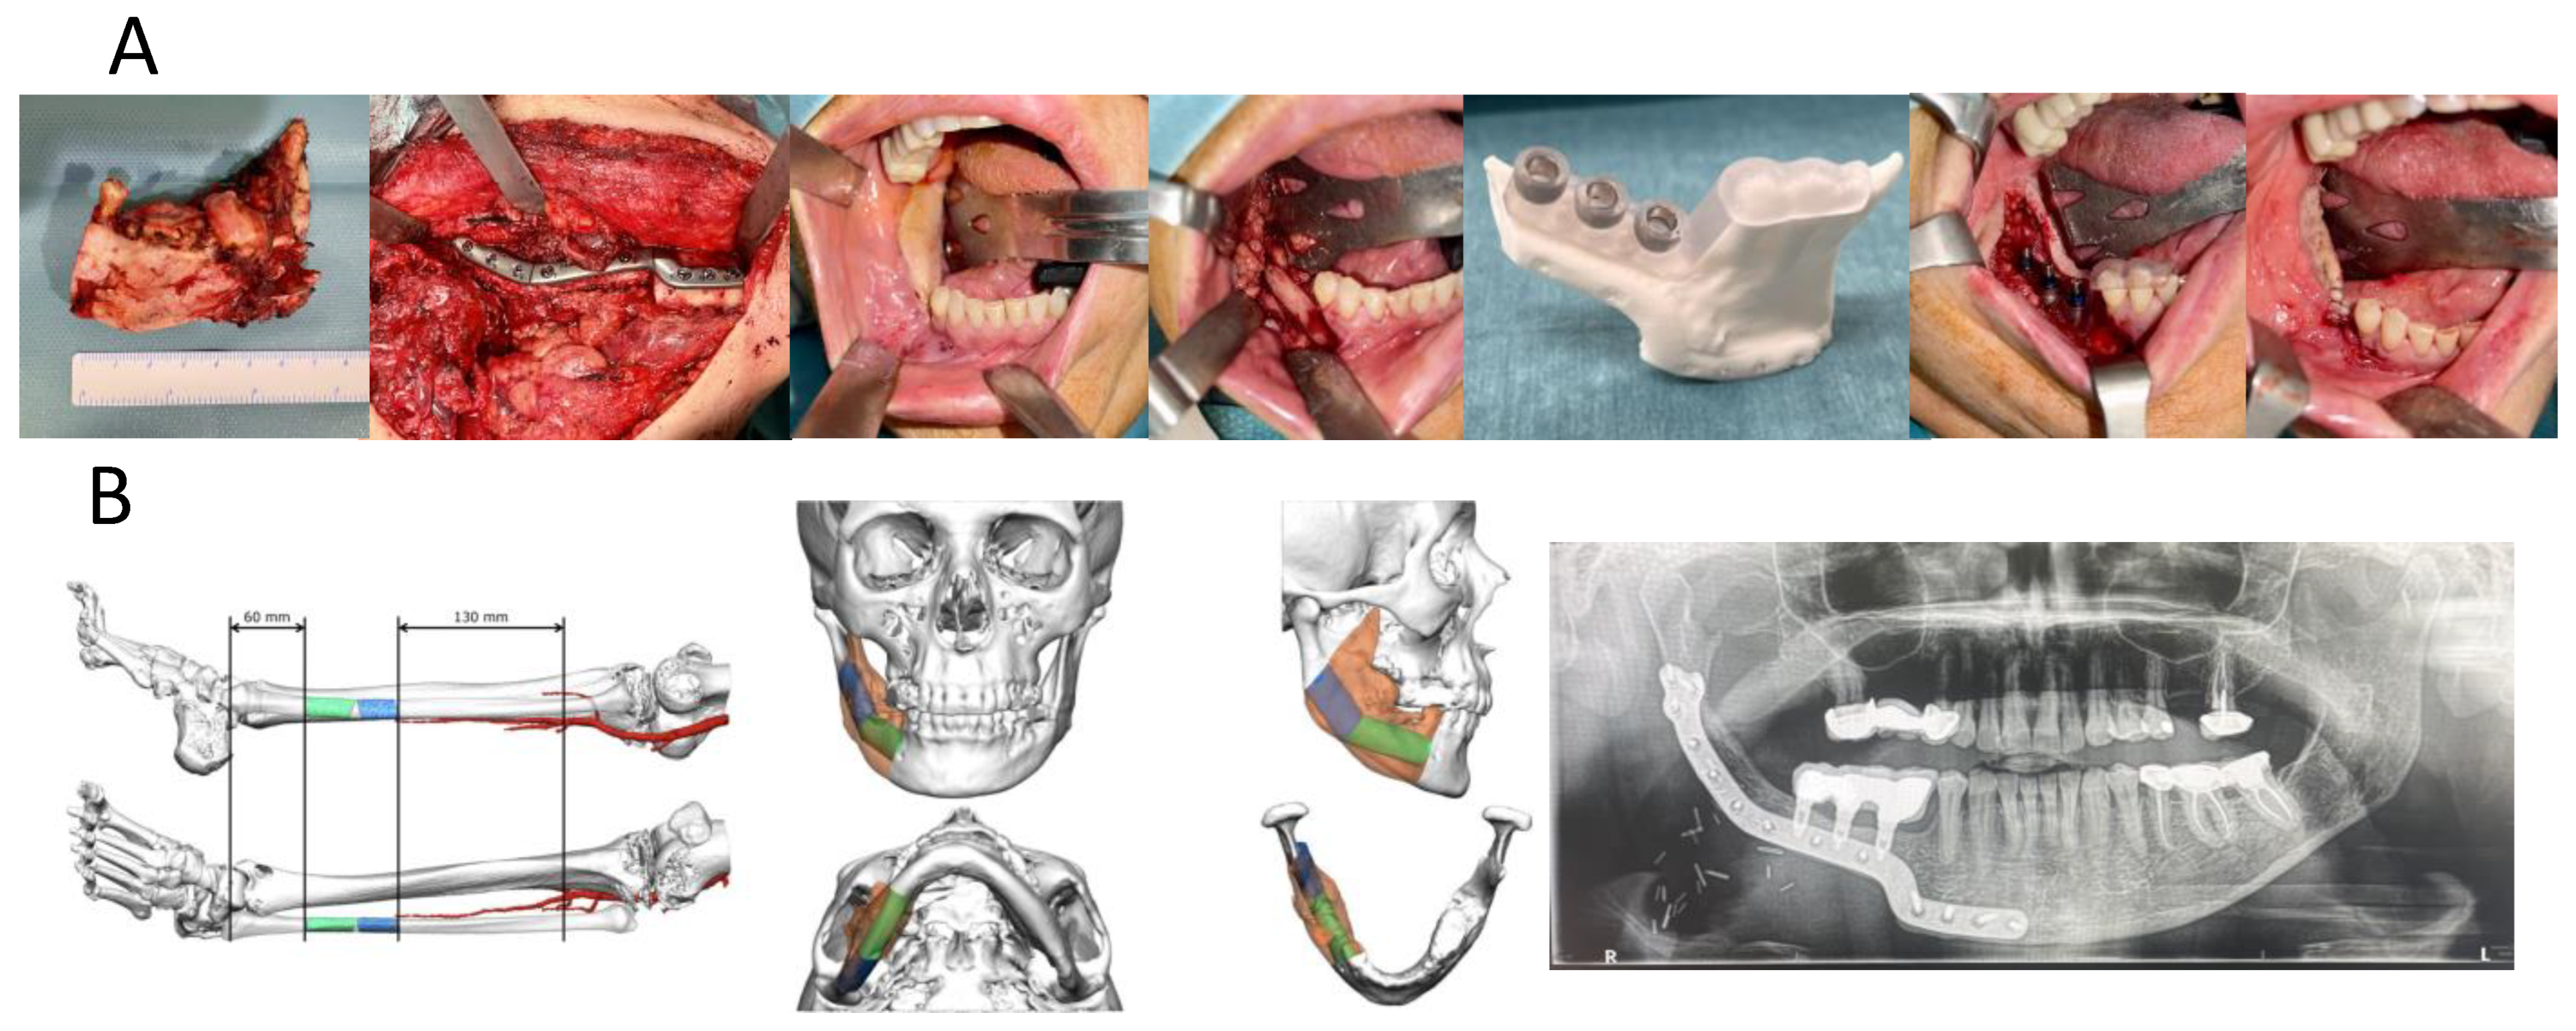

- Imaging: acquisition of preoperative CT or CBCT scans (voxel size ≤ 0.4 mm) in DICOM format.

- Segmentation and planning: creation of three-dimensional anatomical models using open-source or commercial software (3D Slicer version 5.2.2, Materialise 3-matic version 20.0Blender version 2.75 (Blender Foundation)). Implant positioning was prosthetically driven and jointly verified by the surgeon and engineer.

- Guide design: creation of bone-, tooth-, or mucosa-supported templates incorporating metallic sleeves or printed guidance channels.

- In-house manufacturing: stereolithographic printing on Form 3B/3BL systems (Formlabs Inc., Somerville, MA 02143, USA) using Class I biocompatible resins (BioMed Clear, Dental SG, or LT Clear).

- Intraoperative placement: guided implant insertion according to the prosthetically driven plan.

| Reconstruction type | Fibula/Iliac/Native | 20/2/8 | Based on surgical notes |

| No. of implants per case | 3 (1–6) | Derived from operative notes |

| Reconstruction flap | 20 (66%) fibula/2 (6.6%) iliac | From surgical reports |

| Intraoperative deviation | 1.2 ± 0.4 mm (coronal); 1.5 ± 0.6 mm (apical) | Comparable to literature values |